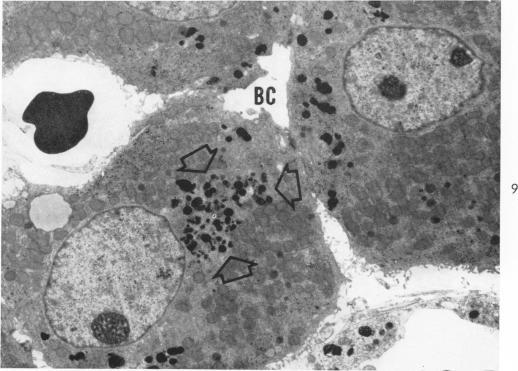

The Movement of Iron-Laden Lysosomes in Rat Liver Cells During Mitosis.

Am J Pathol. 1965 May;46(5):803-27.